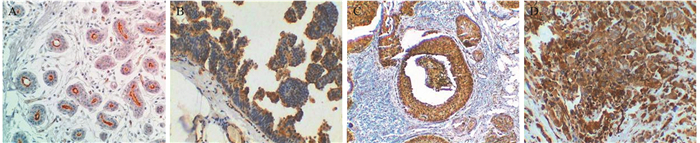

Methods Immunohistochemical SP method was applied to detect the expression and location of podocalyxin in the breast tissues of 62 DCIS (33 cases of low/intermediate grade and 29 cases of high grade) and 129 IDC samples.

Results The expression of podocalyxin in DCIS and IDC were 35.48% (22/62) and 51.94% (67/129) (P < 0.05). It was preferentially expressed in high-grade DCIS, compared with low/intermediate-grade DCIS (P < 0.05). Podocalyxin expression in IDC was associated with tumor grade, pTNM stage and lymph node metastasis in IDC (P < 0.05). Kaplan-Meier univariate analysis revealed positive podocalyxin expression and other factors had significance for disease free survival. Cox model analysis revealed positive podocalyxin expression and lymph nodes metastasis were dangerous independent prognosis factor for IDC.